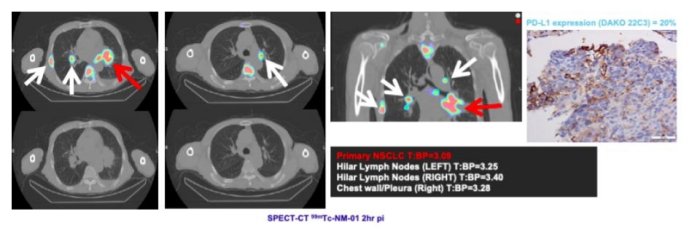

Patient: Male, 75 years old, chest x-ray showed lung shadow. CT scan confirmed multiple lesions. Biopsy confirmed squamous cell carcinoma, a lower left lobe lung hilar tumour, 44 x 48 mm is size with multiple metastases, nodal and distant. 99mTc-NM-01 scan results had uptake in primary tumour and multiple metastatic lesions, a strong positive image. PD-L1 IHC likely understated PD-L1 expression for this patient, PD-L1 treatment prognosis for such a patient is expected to be favourable, though further investigation is required.